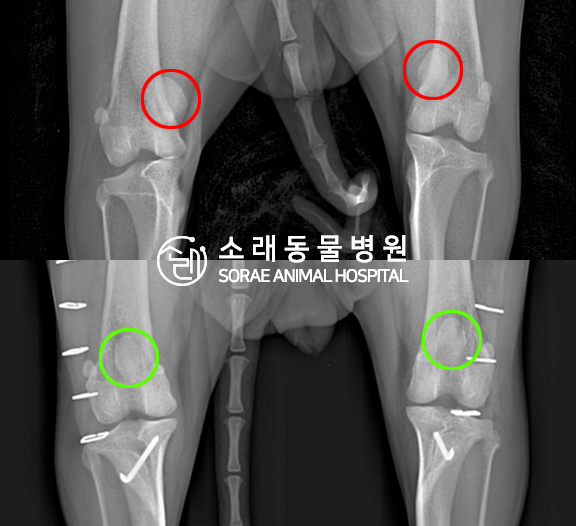

수술전과 수술후에 촬영한 땅콩이의 슬개골

방사선 사진입니다. 나란히 놓고 비교해보니

슬개골의 위치에 확연한 차이가 있는 것을

확인해 볼 수 있는데요. 내측으로 탈구되어 있던

슬개골이 원래 제자리인 활차구에 예쁘게